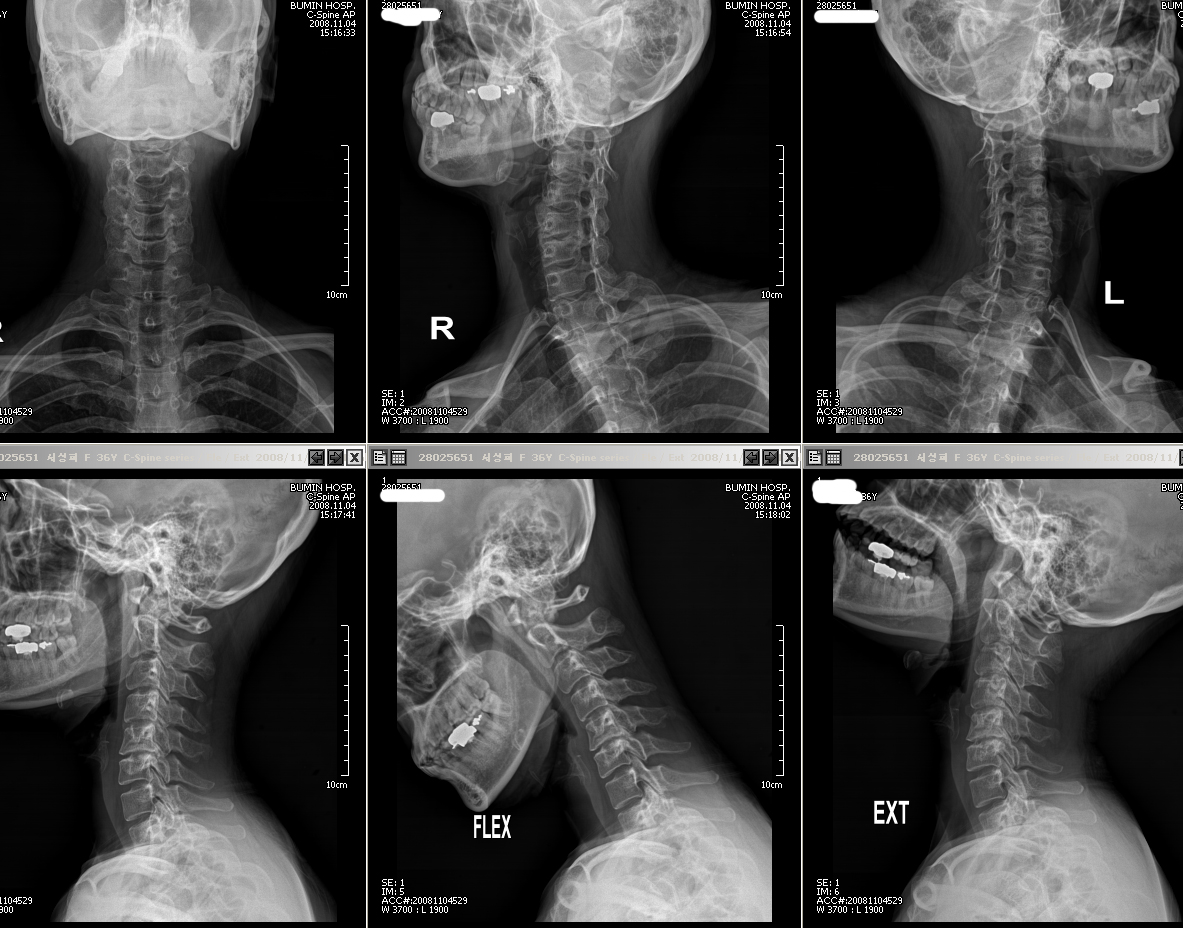

. . . . . . . . . . . . . . . . . . . . . . . . . . . . . . . . . . . . . . . . . . *@#$@#$)ڸ ũ6~7 X-RayԴϴ. 迵ռ ÿ ϼ * ֹǰ (ֹȣ : 5e00b04dc889 / ī,ͳݹŷ ιȣ : 32882635) |